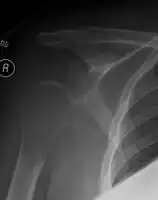

| Solitary plasmacytoma in the long bone of the upper arm | |

1.a. X-ray: solitary plasmacytoma upper arm near shoulder